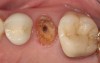

A Class IN maxillary bicuspid was previously restored with a fiber post and an all-porcelain crown (Figure 1). The forces of the oral environment resulted in fracture of the fiber post and crown failure. The remaining fiber post in the root was removed, and anti-rotational areas were prepared for a cast post (Figure 2). A gold cast post was constructed at a dental laboratory, using an indirect technique (Figure 3). A porcelain-fused-to-metal (PFM) crown was constructed with a bevel finish to provide a ferrule and reduce forces on the post (Figure 4 and Figure 5).

Figure 4  The cast post was cemented.

Figure 4

Figure 5  The final crown.

Figure 5